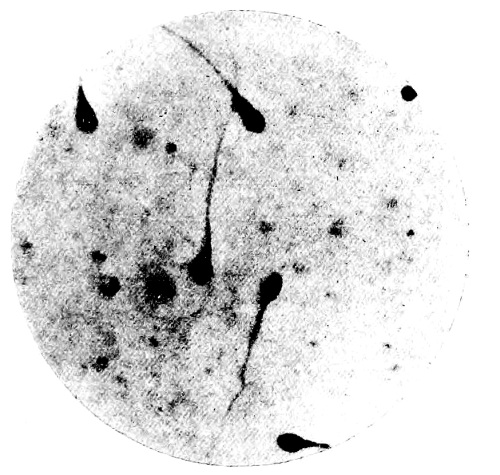

21. Photo-micrograph of Human Spermatozoa 147